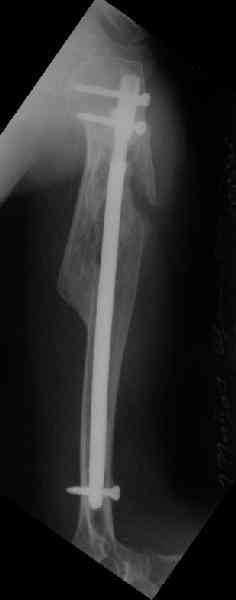

Здесь нет необходимости в серкляже. Вмешиваться на промежуточных отломках приходится, если есть угроза перфорации кожи, или промежуточный отломок попал в фасцию, как пуговица в петлю. В приложении сегментарный оскольчатый перелом плеча в проксимальном отделе, фиксированный больщеберцовым стержнем. Как видите, обошлось без серкляжа. Функция полная.

Пример отличный.

Вот что значит лечить перелом, а не рентгенограмму!

Александр, великолепные снимки! Вопрос - что за гвоздь?

Это укороченный большеберцовый стержень, которые делает предприятие "ЦИТО".

на синтезовский UTN похож))

Скажите пожалуйста, Александр Николаевич, почему Вы использовали большеберцовый гвоздь?

Доступные на тот момент гвозди для плеча имели худшие возможности фиксации в коротком проксимальном отломке.

Уважаемый Александр Николаевич! На продемонстрированных вами рентгенограммах имеется достаточно большое на мой взгляд смещение отломков после фиксации блокируемым гвоздем. На счет полной функции все понятно, а нет ли каких либо сосудистых расстройств конечности? Имею ввиду венозную недостаточность или лимфостаз.